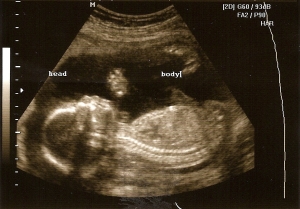

I am always nervous before I go for a sonogram. I find myself watching the discovery health shows the night before. I spend the rest of the evening convincing myself all will be well when they tell me I am in fact having a dwarf baby the next day. The weird part is, I do think I would be okay.

We sat in the waiting room with a wiggly Lucy requesting that we draw various animals on the back of crumbled up papers found in my bag. I laughed at Jorge’s attempts at a cow.

Renee never opens the waiting room door, she just calls my name in a loud bellow from the next room.

“I remember you, I did this pretty one right here right? That was a long time ago and you’re back again.” the big, lovely African- American woman says.

“He just keeps getting me in trouble, what can I say?”, I reply.

“Like you weren’t there?” she says with one eyebrow raised. I laugh.

“Yeah, thanks Renee.” Jorge agrees.

Lucy, Jorge and I file into the dark room. Lucy would prefer to lay on the table with me except I barely fit on the table myself. “Scoot over, there’s room for her.” the older woman persists. I give in because there is no crossing Renee or Lucy for that matter. They understand each other even though the last time they met was when Lucy was only a shadow on the screen above.

We all stare in amazement at how busy this baby is. Jorge’s goofy grin returns, it’s the one reserved for all things baby.

“My, my, look at that.” Renee says.

“Spill it Renee, we’re dyin’ here.” I say.

She makes us wait as she spells our news on the screen. Girl. I instantly feel a camaraderie with Lucy and her sister. We are the girls now, equal in number to the boys. It’s all too cheesily perfect. I never walk in with preferences and I always walk out feeling that things are exactly as they should be. Everyone is especially giddy today.

“Oh wow!” Jorge says. I smile.

“I’m hungry mama.” Lucy says. “Didn’t you bring her some snacks?” Renee asks.

“I know, I know, I was too excited, I forgot.” Renee ignores me in deep effort to get her measurements. This baby girl is not cooperating. She is way too busy to stay still for pictures. The minutes pass and I gently urge her to be kind to Renee.

“Oh, she’s not gonna do it, she has too much goin’ on girl.” Renee insists. My girl stops for a brief second and Renee gets the shot. “I guess she’s listenin’ to you.”

We laugh, tell a few more stories, and gather our things to leave.

“You have a good Mother’s Day now. ” she instructs as we leave.

“Do you have any babies of your own Renee?” I ask.

“No, just these babies here…” she says.

“Well, that’s lots of motherin’, so Happy Mother’s Day to you….”

It’s just that some woman carry the motherin’ for us all. They call us out, they listen and nod, laugh when we are being ridiculous, they remind us of truth within, they remember the place we are in, they bring peace to our chaos, they are constant.

All the mothers in the world, so divinely placed, we honor you. Please feel our love and know we would be a puddle on the ground with out you. Of course, you would tell us we would be just fine.

And we are, just knowing you are there, in dark sonogram rooms, grocery store aisles, next door, a phone call away…